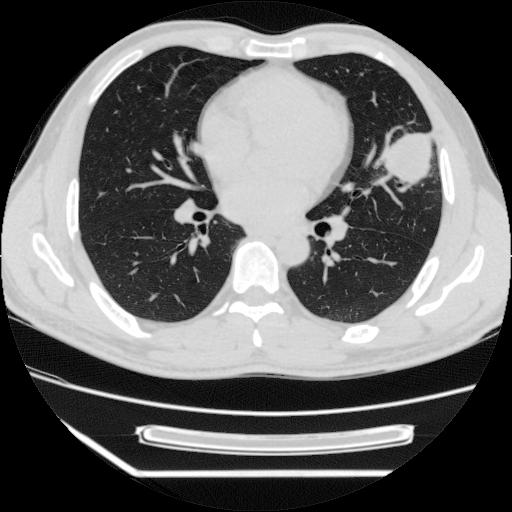

男,38岁,于2009年8月9日晚突发左侧胸痛,今x线提示左下肺阴影,为了明显确诊断,行ct检查,

血常规:嗜酸性细胞增高,单核细胞增高。

病灶发生在下叶,密度均匀,边缘模糊、毛糙,周围血管纹理增强扭曲改变,靠近胸膜处病灶胸膜反应明显。

支持考虑---球形肺炎。

左肺舌叶病变。主体病灶呈类圆形中心密度低,成液化趋势周边班片影分布

考虑肺脓肿

虽然实验室检查支持炎性病变,且病变内有坏死改变(中央呈大片状低密度影),但仍不能掉以轻心,鳞癌也可以有这种影像改变。